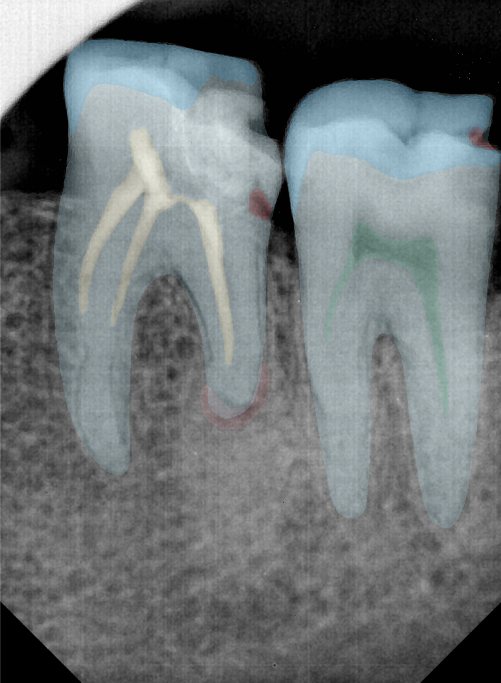

CR/DR 牙齿分割阶段记录

当前进展

- 完成了 CR/DR 牙齿相关分割训练

- 当前结果已经达到阶段预期,但仍有细节问题需要继续处理

相关测试

遇到的问题

- 训练过程中出现过 mask 下移问题

- 部分结果会出现 box 填充异常

- mask 边缘仍然有比较明显的锯齿感

参考